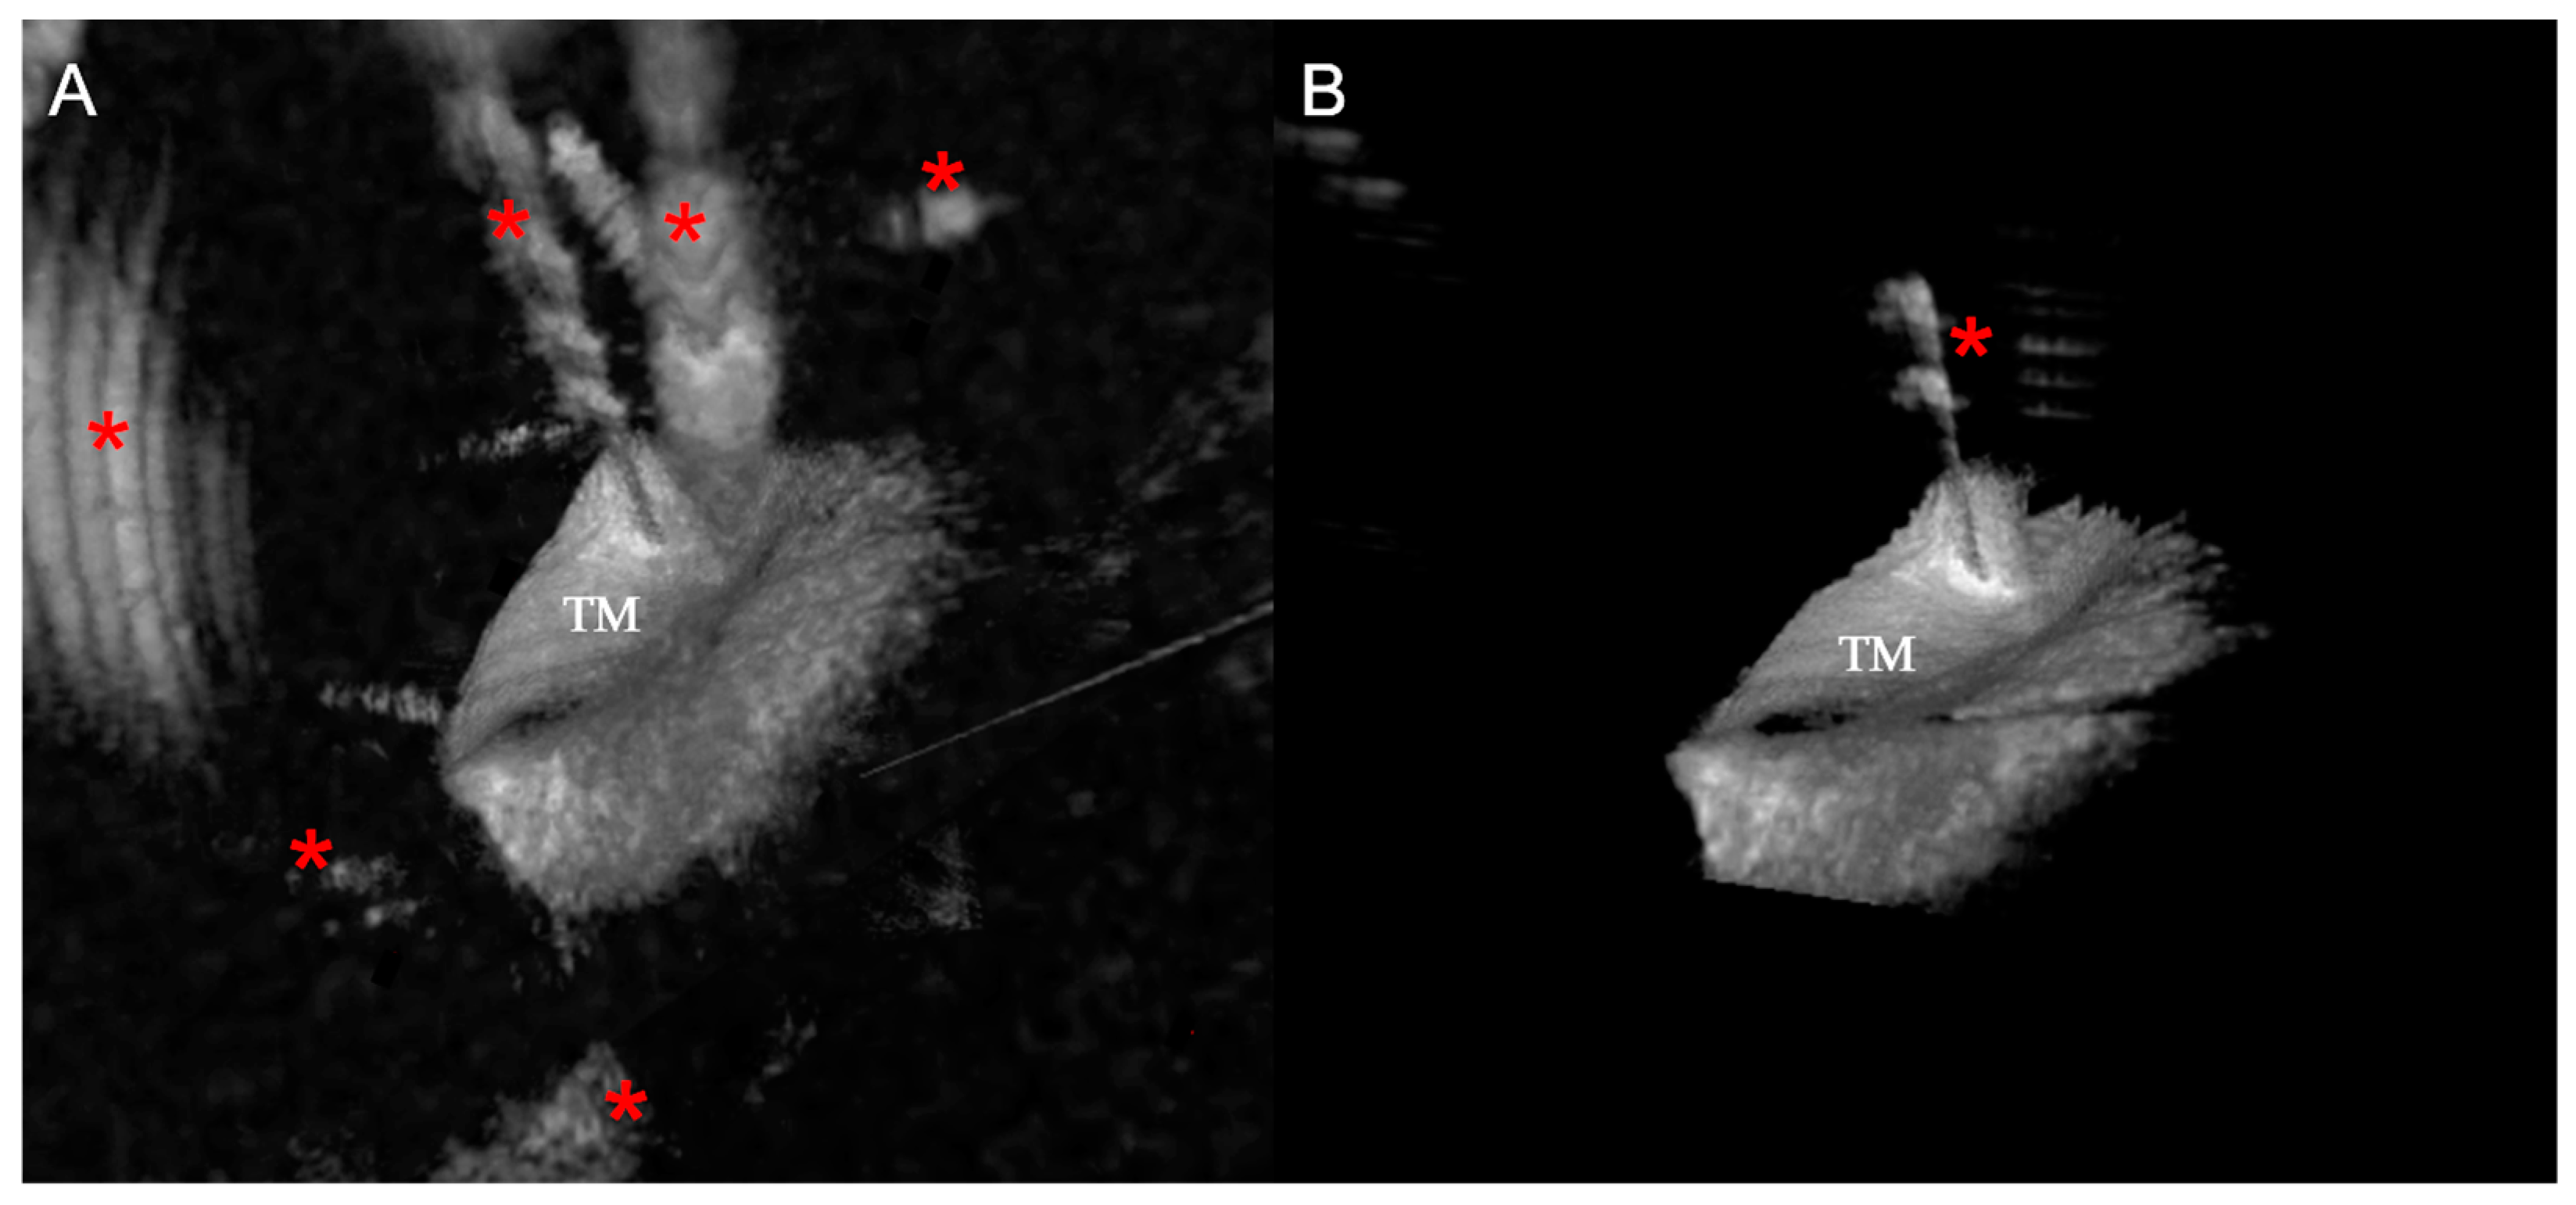

2.3. Large Object Detection Algorithm

2.4. Small Object Detection Algorithm

2.5. Image Recognition Algorithms